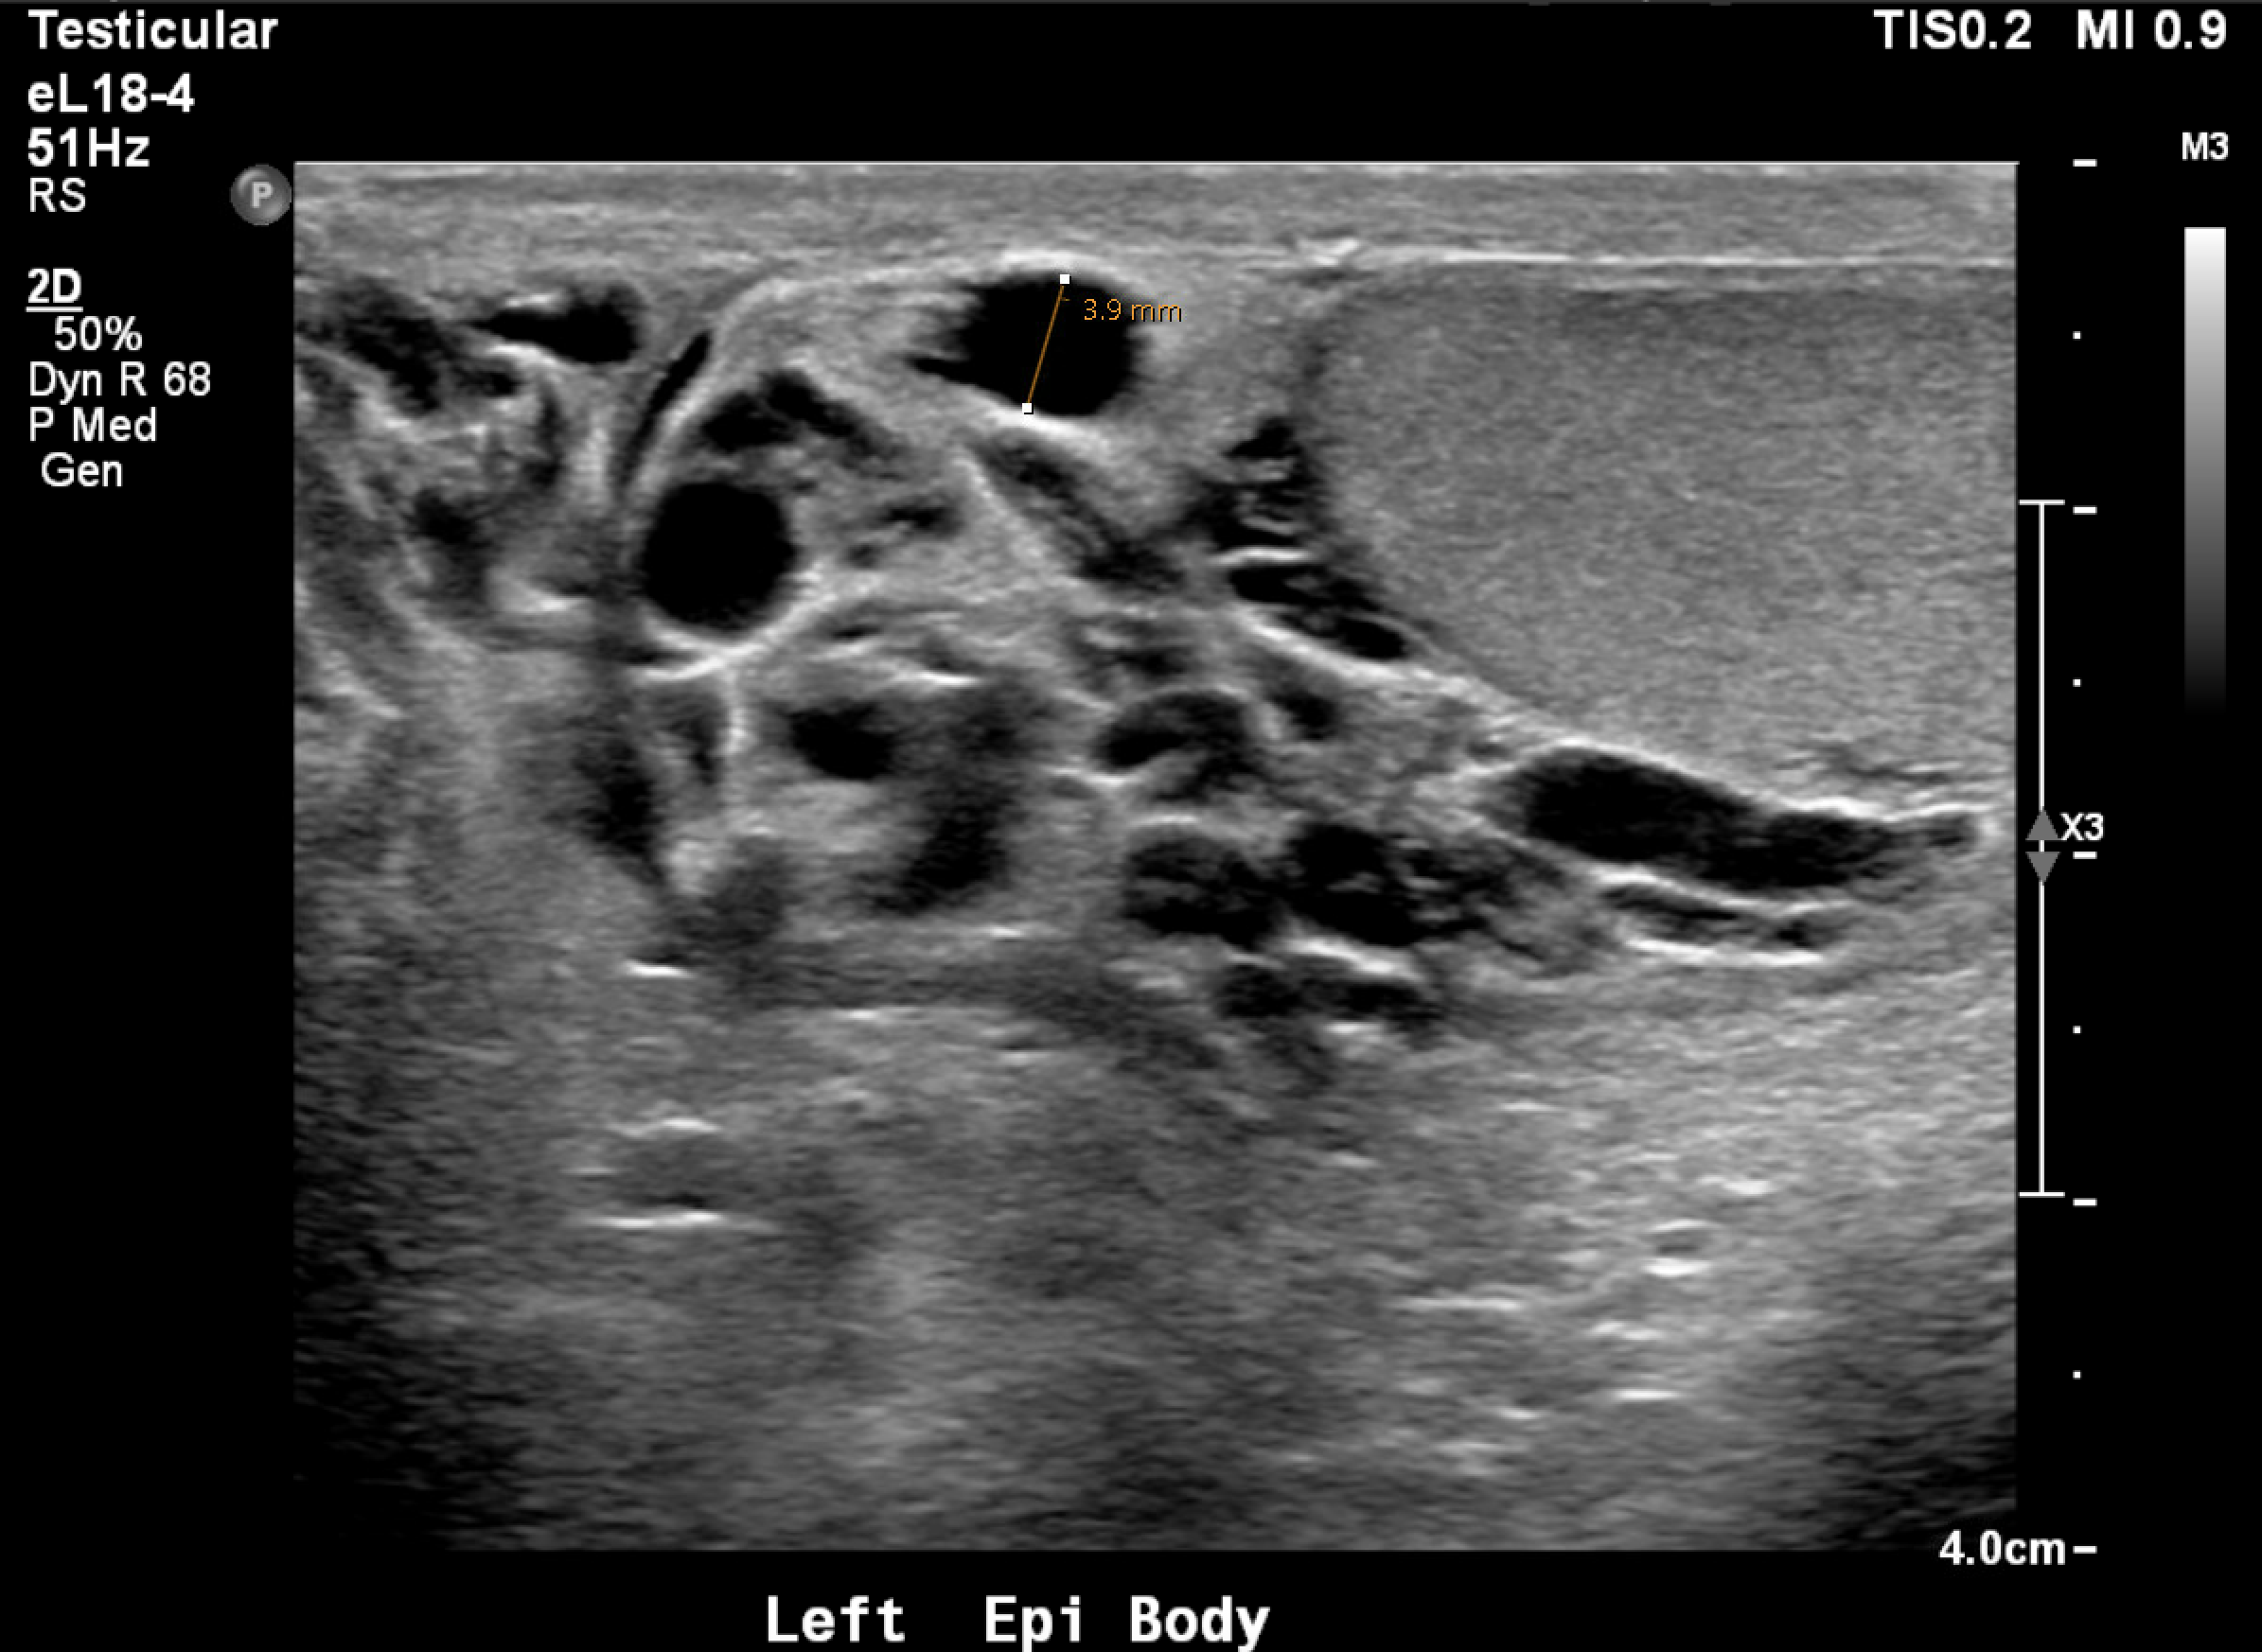

Sonographic Criteria

Pampiniform plexus veins >3 mm in diameter

Reflux >1 second on Valsalva (color or spectral Doppler)

Examination in standing position (supine alone underestimates)

Color Doppler ultrasound demonstrating dilated pampiniform plexus veins >3 mm with venous reflux — characteristic of a left varicocele.Color Doppler ultrasound showing dilated pampiniform plexus veins — venous flow confirmed on color signal without spectral waveform acquisition.